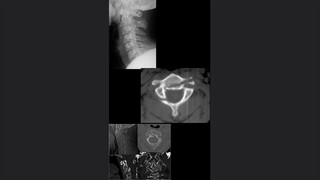

Radiología forense

Características históricas de la radiología forence